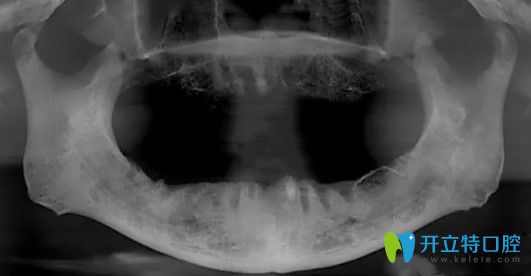

在天津中諾口腔做的正畸

【評價】:一直在中諾口腔醫(yī)院孟濤主任這里看牙,摘下牙套后做的檢查和之前的檢查對比,簡直發(fā)生了翻天覆地的變化啊,真的和整容差不多,在這期間多虧孟主任的認真負責(zé),每次見面和復(fù)診都有說有笑,真的是一個稱職的好醫(yī)生好朋友,取得的今天的成果真的滿意,再次謝謝孟濤主任對我的照顧。